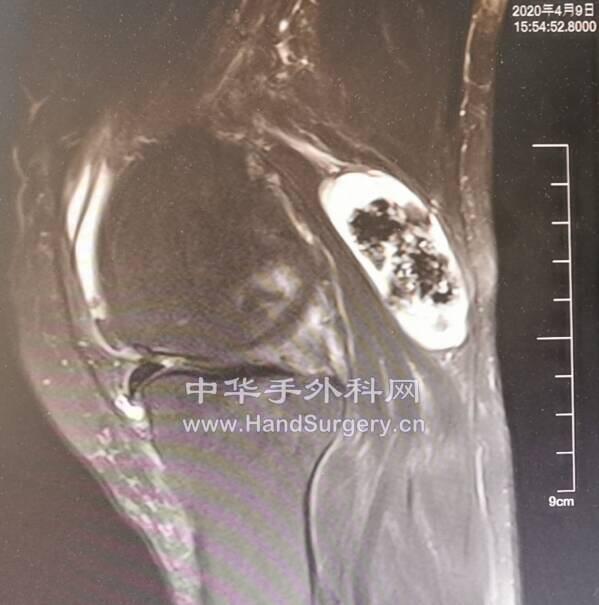

肛肠肿瘤患者,行盆腔核磁检查无意间发现股骨头肿物

囊肿影像局限,孤立,不在负重区,暂不考虑骨坏死。

会诊意见:考虑孤立性骨囊肿,不除外转移

明日一腘窝囊肿待术

12.png

13.png

患者女性,74岁

发现肿物2年,近3个月增大,走路时胀痛

肿物中间钙化,与关节囊相通

位于腘窝偏内侧,与神经血管束毗邻紧密